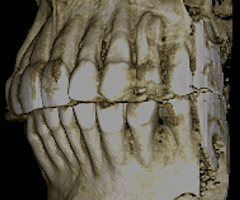

При анализе и описании компьютерной конусно-лучевой томографии (рис. 2а-г) была выявлена генерализованная первичная дегисценция вестибулярной пластинки кости от 1/2 до 3/4 длины корней зубов, зубной ряд целостный, все зубы витальны, кариозных поражений нет. Тип кости 1-2 (Lechkolm и Zarb, 1983), первичная дегисценция вестибулярной костной пластинки превышает пределы возрастной атрофии.

Через 12 месяцев (рис. 7а-г) на срезах компьютерной томограммы 11-ый и 13-ый зубы находятся в костной ткани, при этом костные пики и перегородки укрепились, объем их увеличился; вестибулярно заметен объем костной массы, предположительно компактной формации, исходя из электронной плотности участка. Этим объясняется отсутствие рецидива при лечении рецессии десны как в случае применения аутотрансплантата, также и ТМО (dura mater).